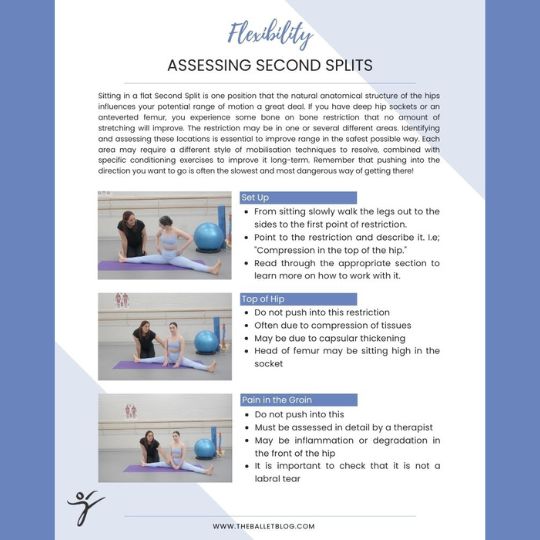

Another position I see young students trying to achieve in order to get more flexible is oversplits in second position. Unfortunately stretching young hips past their natural physiological range runs the risk of permanent damage, so we need to be very careful in how we achieve mobility in this position. Any flexibility training requires an intelligent and multifactorial approach, with a deep understanding of human anatomy guiding its application. Doing this ensures that young dancers will be able to continue dancing well into adulthood and live a normal, pain free life when they do decide to stop performing.

Just to clarify - I have no issues with extreme mobility when achieved safely, and with the appropriate control. In fact, much of the work I do with the high level, elite students is focused exactly on this. However we focus on achieving this through educated and intelligent, up to date, smart ways, to avoid any potential issues, and the students are educated to manage their own bodies. This means that they will be able to continue dancing well into adulthood, and be able to live a normal, pain free life when they do decide to stop performing.

Anyone training young students, and the parents of these students need to be very aware of the possible dangers when trying to improve mobility. The students themselves often find it difficult to see the long term consequences of their actions, and for them, achieving a certain position is often their end goal. It is our responsibility to learn the safest possible ways to help them to achieve their goals, as well as educating them on the appropriateness of their goals to their chosen career.